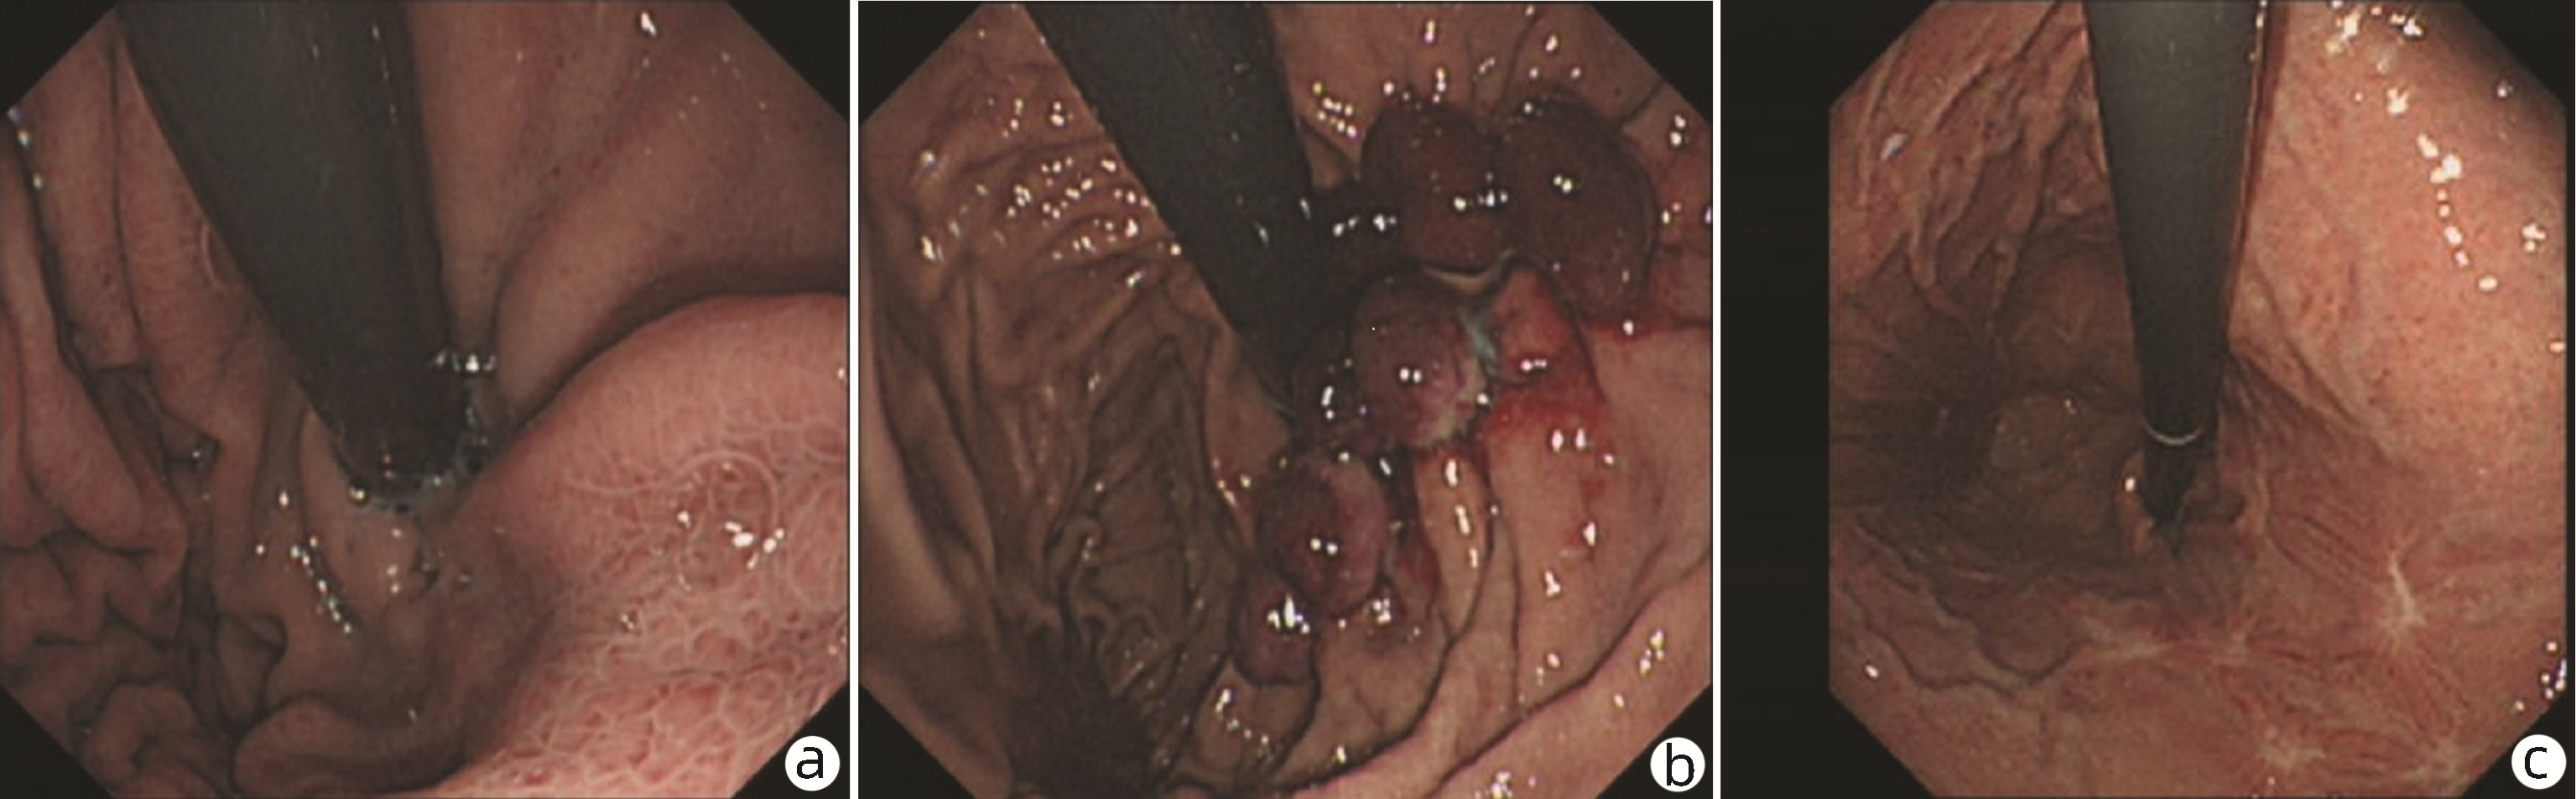

Endoscopic sequential ligation for treatment of esophageal and gastric varices with duodenal varices: A case report

Hao WEN, Zhaohui HE, Tong JIANG, Guoqing SHI

2023, 39(3): 637-639. DOI: 10.3969/j.issn.1001-5256.2023.03.024

Abstract(880) HTML (273) PDF (2676KB)(104)

Abstract: